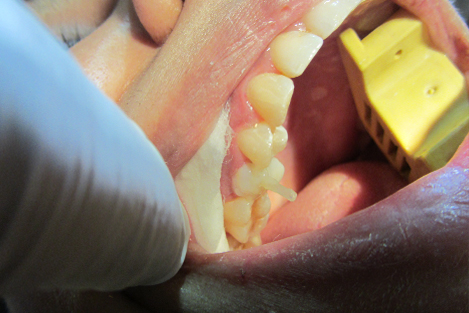

Dental Dam Isolation